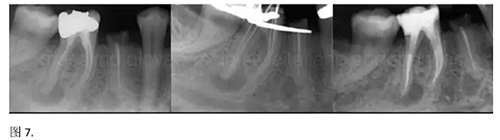

開髓后預(yù)敞、探查根管、建立直線通路是根管機(jī)械預(yù)備的第一步。在這些階段中,醫(yī)生可能會(huì)經(jīng)常遇到一些困難。這些難題包括器械折斷、臺(tái)階形成、根管歧坡或根管拉直、帶狀穿孔、根尖穿孔、根尖肘形、根尖堵塞。所有這些錯(cuò)誤可導(dǎo)致根管系統(tǒng)清潔不完善從而降低牙髓治療成功率。

結(jié)論:本文的目的是描述一種旨在優(yōu)化根管根尖部分預(yù)備的預(yù)敞技術(shù)。根管頸部或冠方的早期預(yù)敞對(duì)于減少初尖銼直徑和根尖部根管直徑之間的差異至關(guān)重要。大量研究表明,手用或機(jī)用器械預(yù)敞根管能顯著減少器械折斷的發(fā)生率。下一篇文章將描述如何建立可重復(fù)的引導(dǎo)路徑。而引導(dǎo)路徑是指鎳鈦器械可沿著光滑根管壁輕易地滑行至工作長(zhǎng)度的通路。